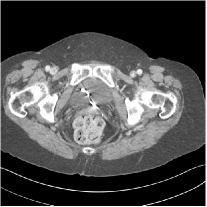

III.C. Low-dose Experiments with Mayo Clinic Data

First, we study transform training based on Mayo Clinic data. As shown in Fig. 6, seven slices obtained at regular dose from three patients are used for transform learning. The number of pixels . Similar to the phantom experiments, overlapping patches are extracted with a patch stride. The number of overall training patches is about . We set for ST, , , for MARS2, , , , , for MARS3, , , , , , , , , for MARS5, , , , , , , , , , , , , for MARS7. The iteration number in Algorithm 1. Fig. 7 illustrates the learned transforms obtained with Mayo Clinic data. Different from the XCAT phantom case, these transforms up to MARS5 display more complex features and structures. The rich features of the MARS models better sparsify the training images over layers compared to the single-layer model (ST).